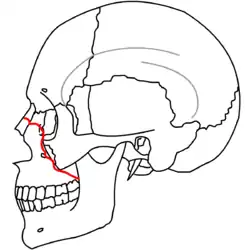

| Fraturas 1 de Le Fort | |

No início do século XX, René Le Fort mapeou as regiões faciais típicas dos traumas maxilo faciais, agora conhecidos como Fraturas I, II, e III de Le Fort (direita).[11] A Fratura I de Le Fort, também chamada de Fratura de Guérin ou Fratura transversa,[12] envolve a maxila, separando-a do palatino.[13] A Fratura II de Le Fort, conhecida também como Fratura piramidal,[12] atravessa os ossos nasais e o aro orbital.[13] A Fratura III de Le Fort, por sua vez, chamada também de Disjunção crâniofacial,[12] atravessa a frente da maxila e envolve as suturas zigomaticofrontal, maxilofrontal nasofrontal, os assoalhos das órbitas, a etmóide e o esfenóide.[12] As Fraturas de Le Fort, responsáveis por 10-20% das fraturas faciais, são frequentemente associadas com outros ferimentos graves.[13] Le Fort fez seu trabalho com base em cadáveres e caveiras, e o sistema de classificação tem sido criticado como impreciso e simplista uma vez que a maioria das fraturas de meia-face envolvem uma combinação das fraturas de Le Fort.[13] Embora a maioria das fraturas faciais não seguem os padrões descritos por Le Fort, seu sistema ainda é utilizado para categorizar os diversos tipos de traumatismos.[14] http://www.angelfire.com/nm/cirurgia/pritra/Image90.gif